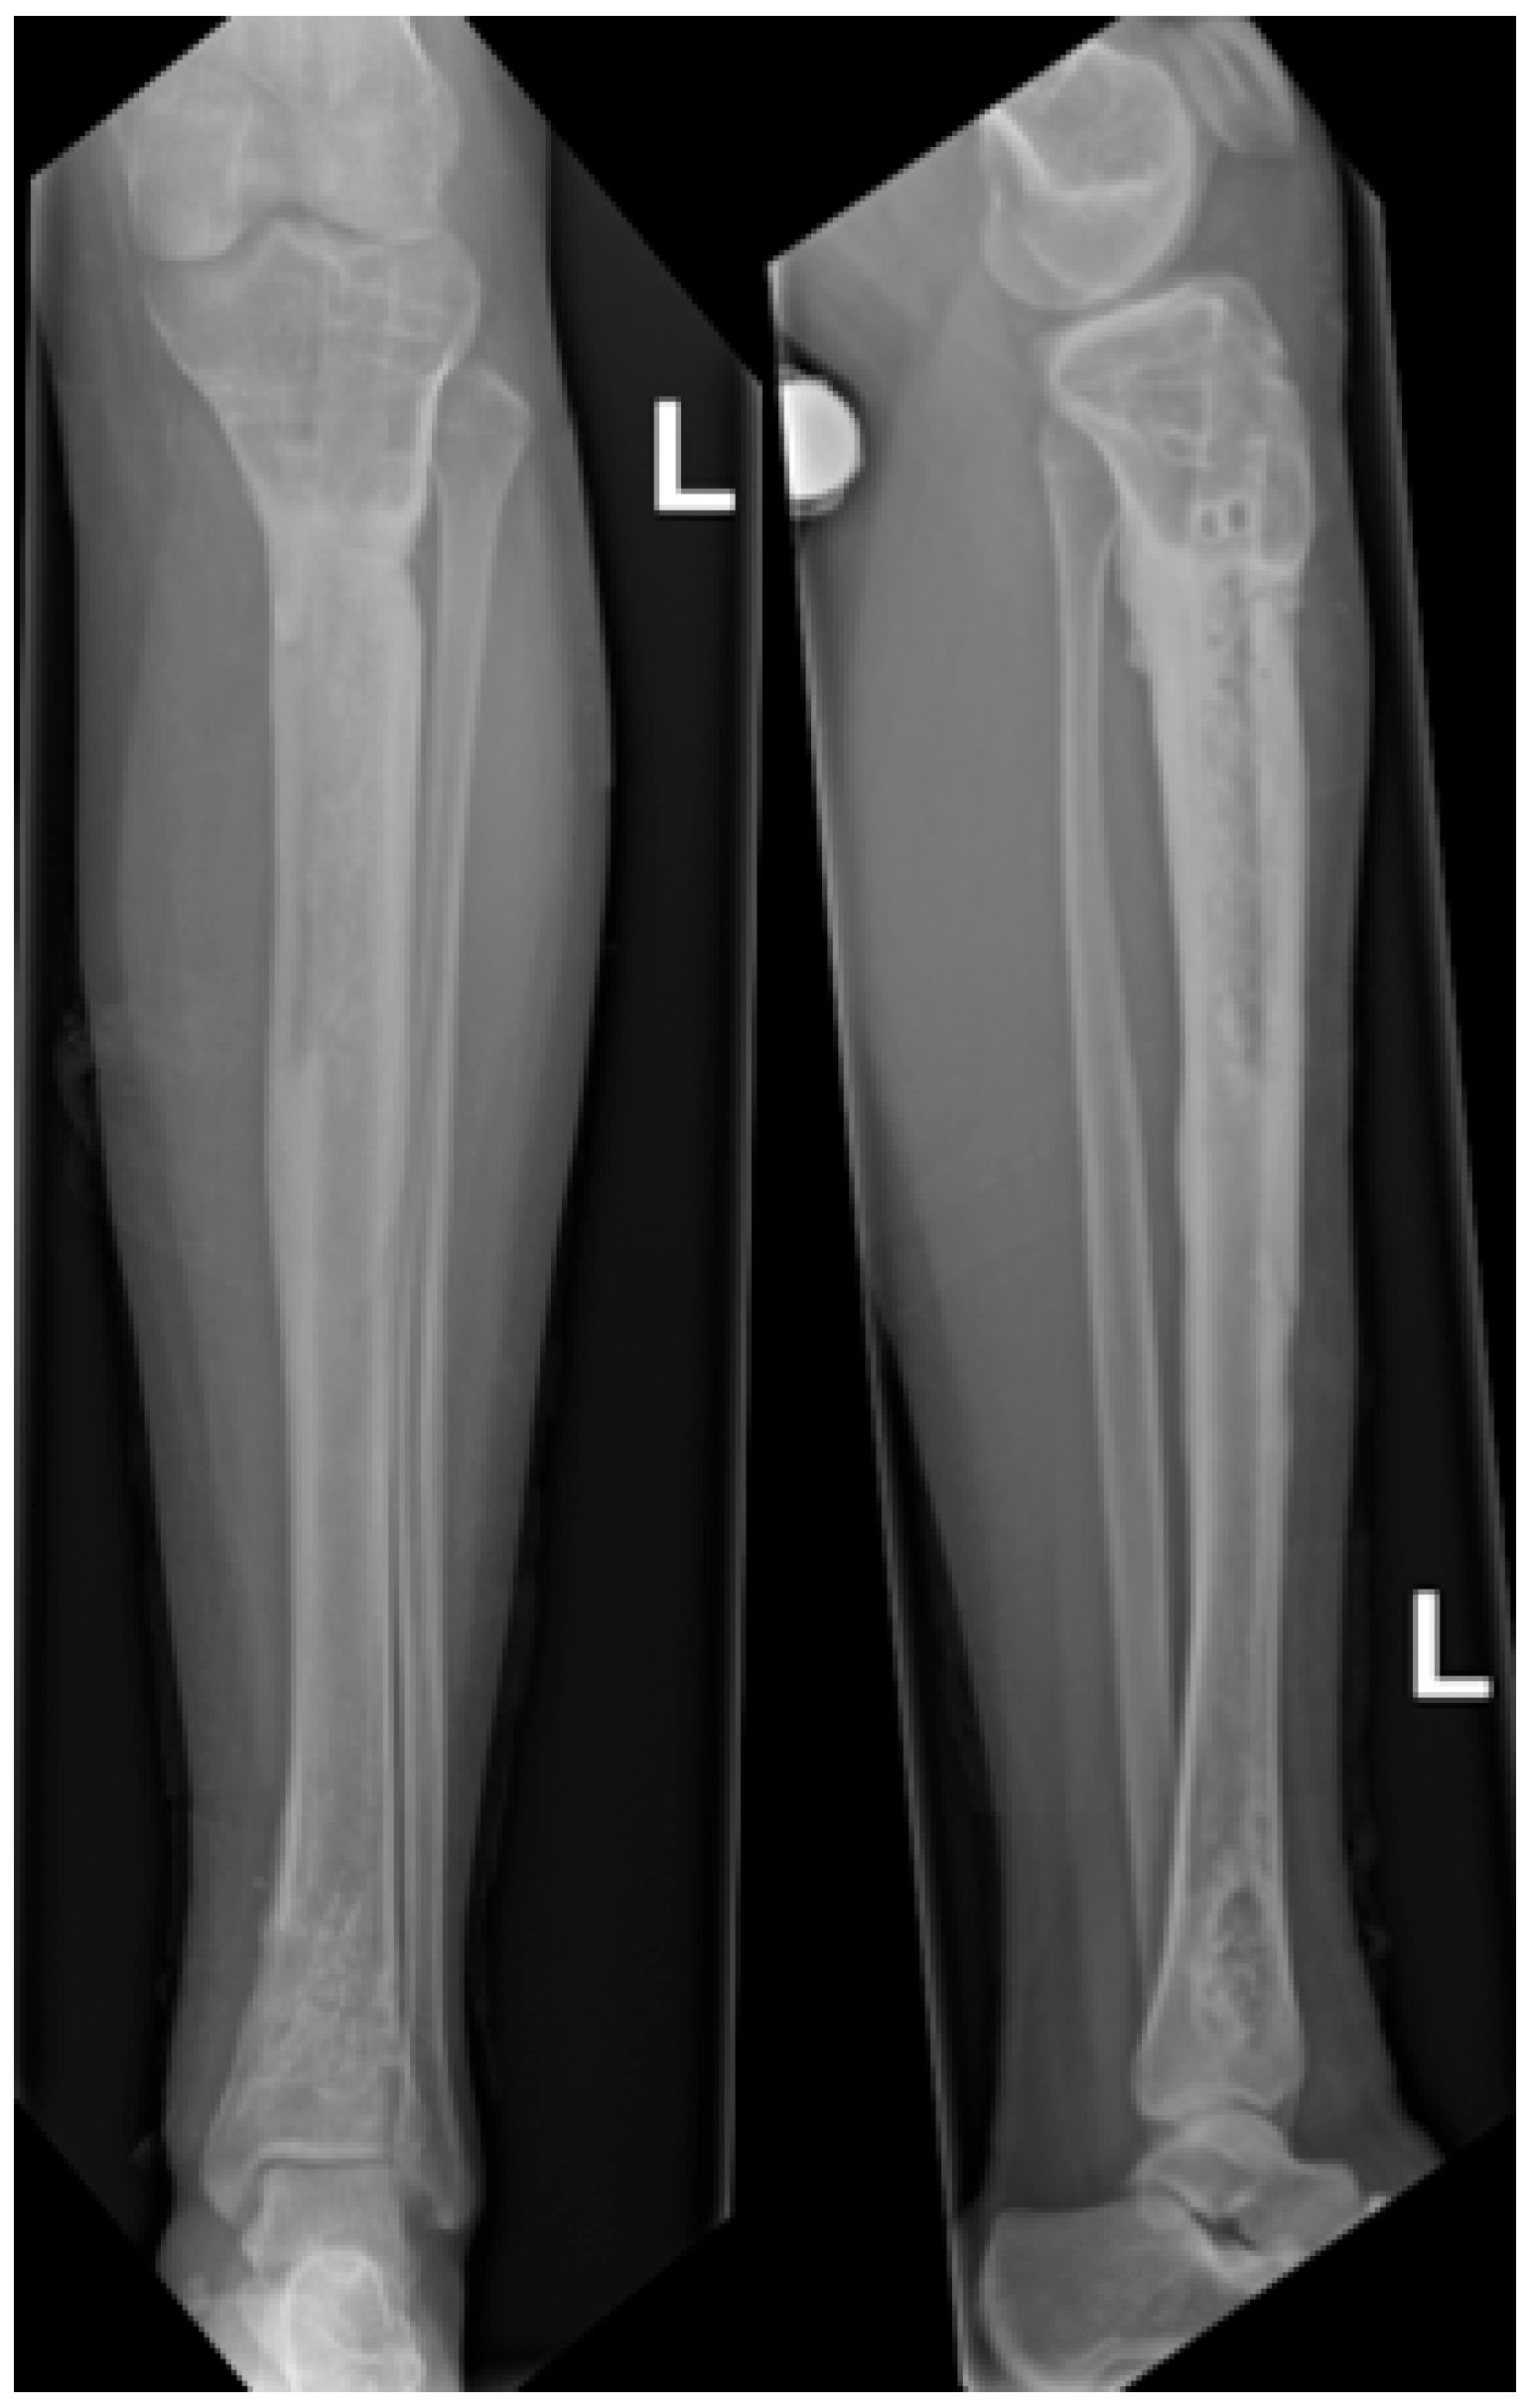

Figure 1.

Preoperative radiographs showing an osteofibrous dysplasia-like adamantinoma (OFD/LA) in the left tibial diaphysis. (A) Anteroposterior view. (B) Lateral view.